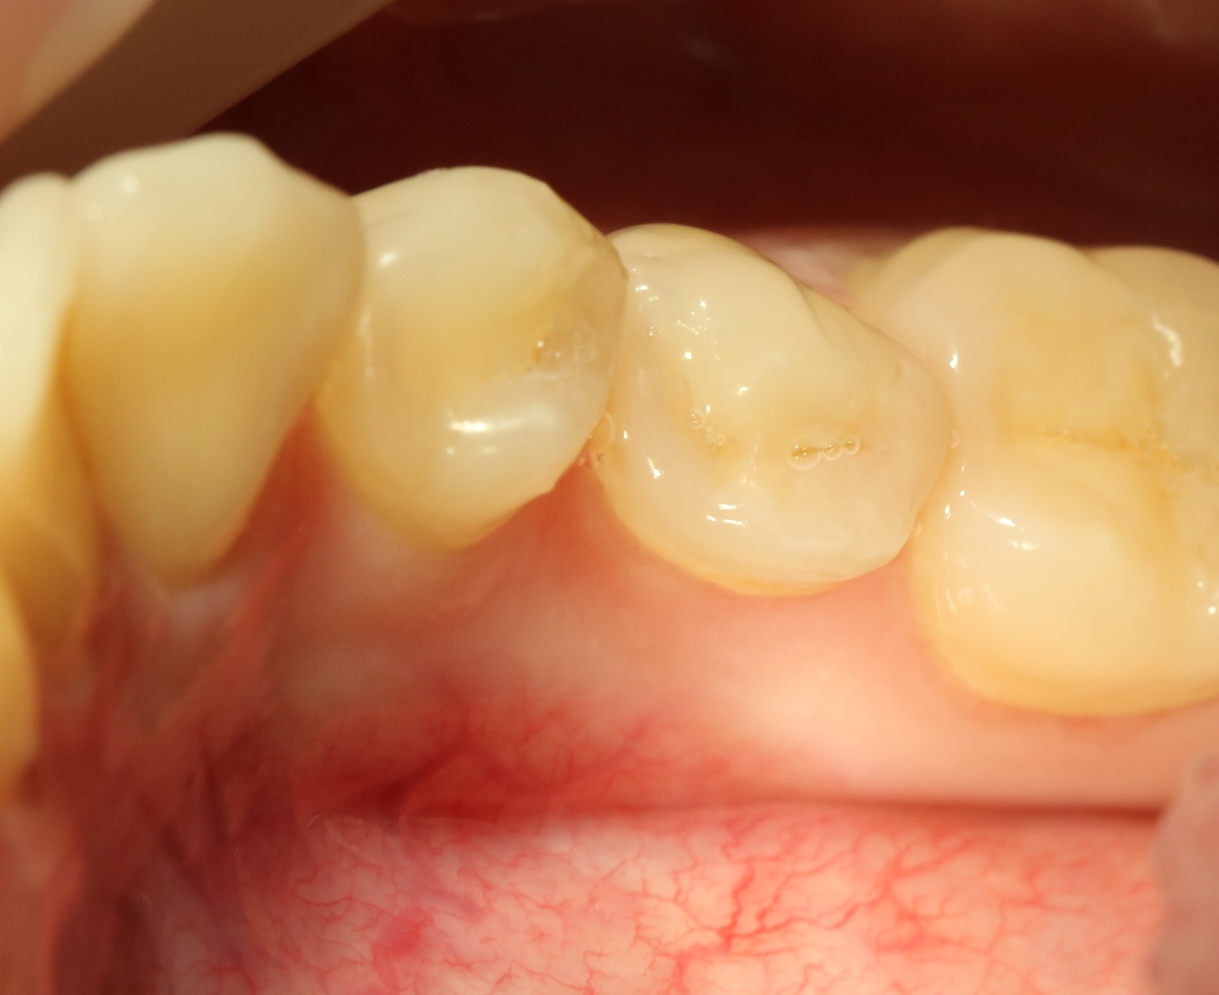

У моей пациентки случайно мы обнаружили два ретинированных сверхкомплектных премоляра:

При этом, весь комплект зубов на месте (за исключением правой верхней восьмерки — моя работа).